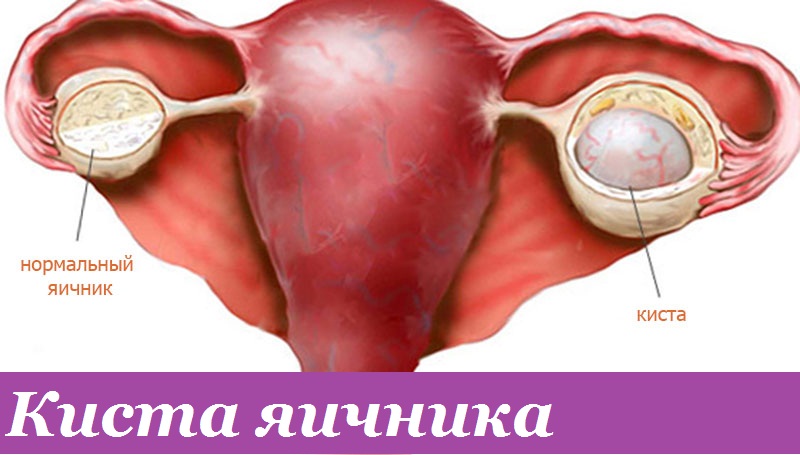

Гистологические изображения фолликулярной кисты яичника